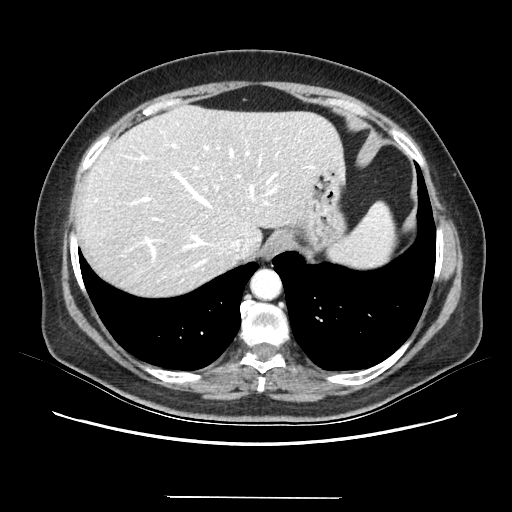

Original VENOUS CT scan

Full window (WL 1023.5, WW 4095 β†’ Low βˆ’1024, High +3071)

Actual HU range: [-160.0, 240.0]